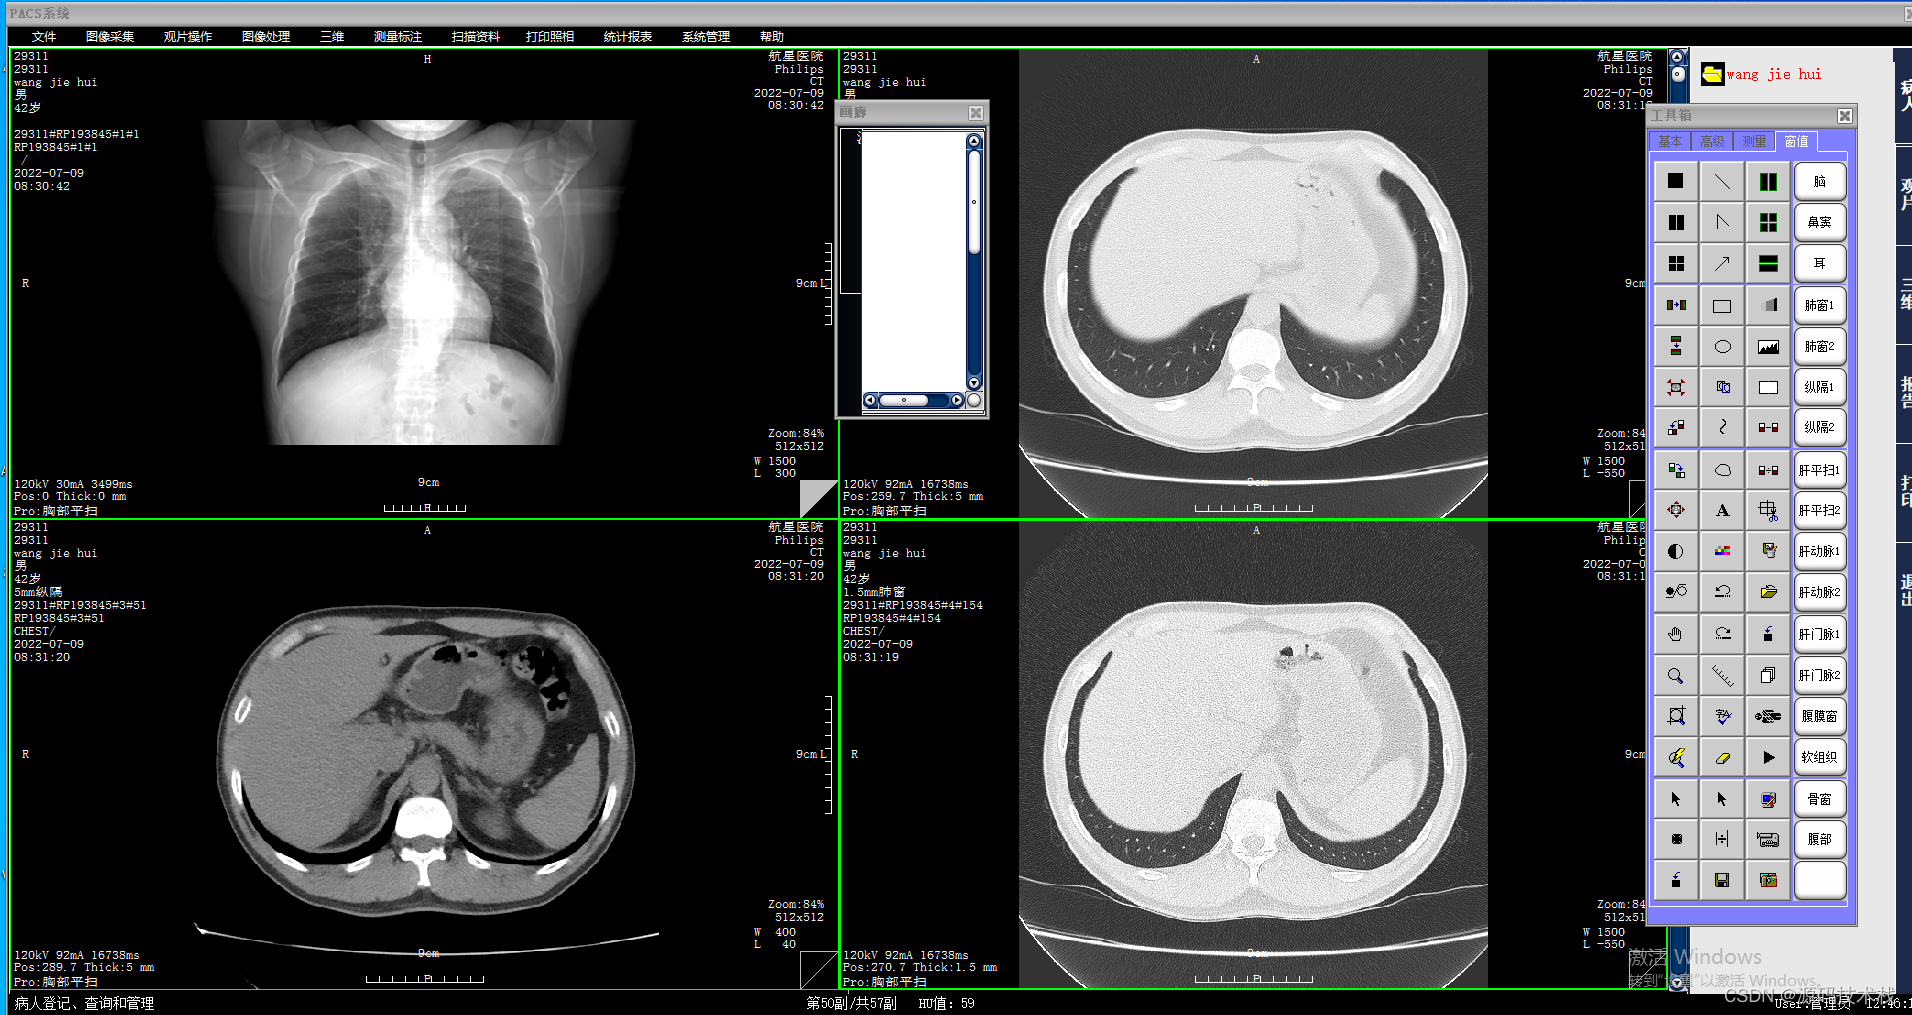

10.在多显示屏环境下可自动设定影像显示模式以适合屏幕大小及分辨率;

12.可同时调阅一个患者或多个患者不同诊断序列、体位、时期;

15.支持多幅排列显示方式,自动窗宽窗位优化调整;

16.可配置图例目录和窗口排列、桌面方式(工具栏、命令按钮、快捷键等)、交互式窗口、优化设置、灰度反转;